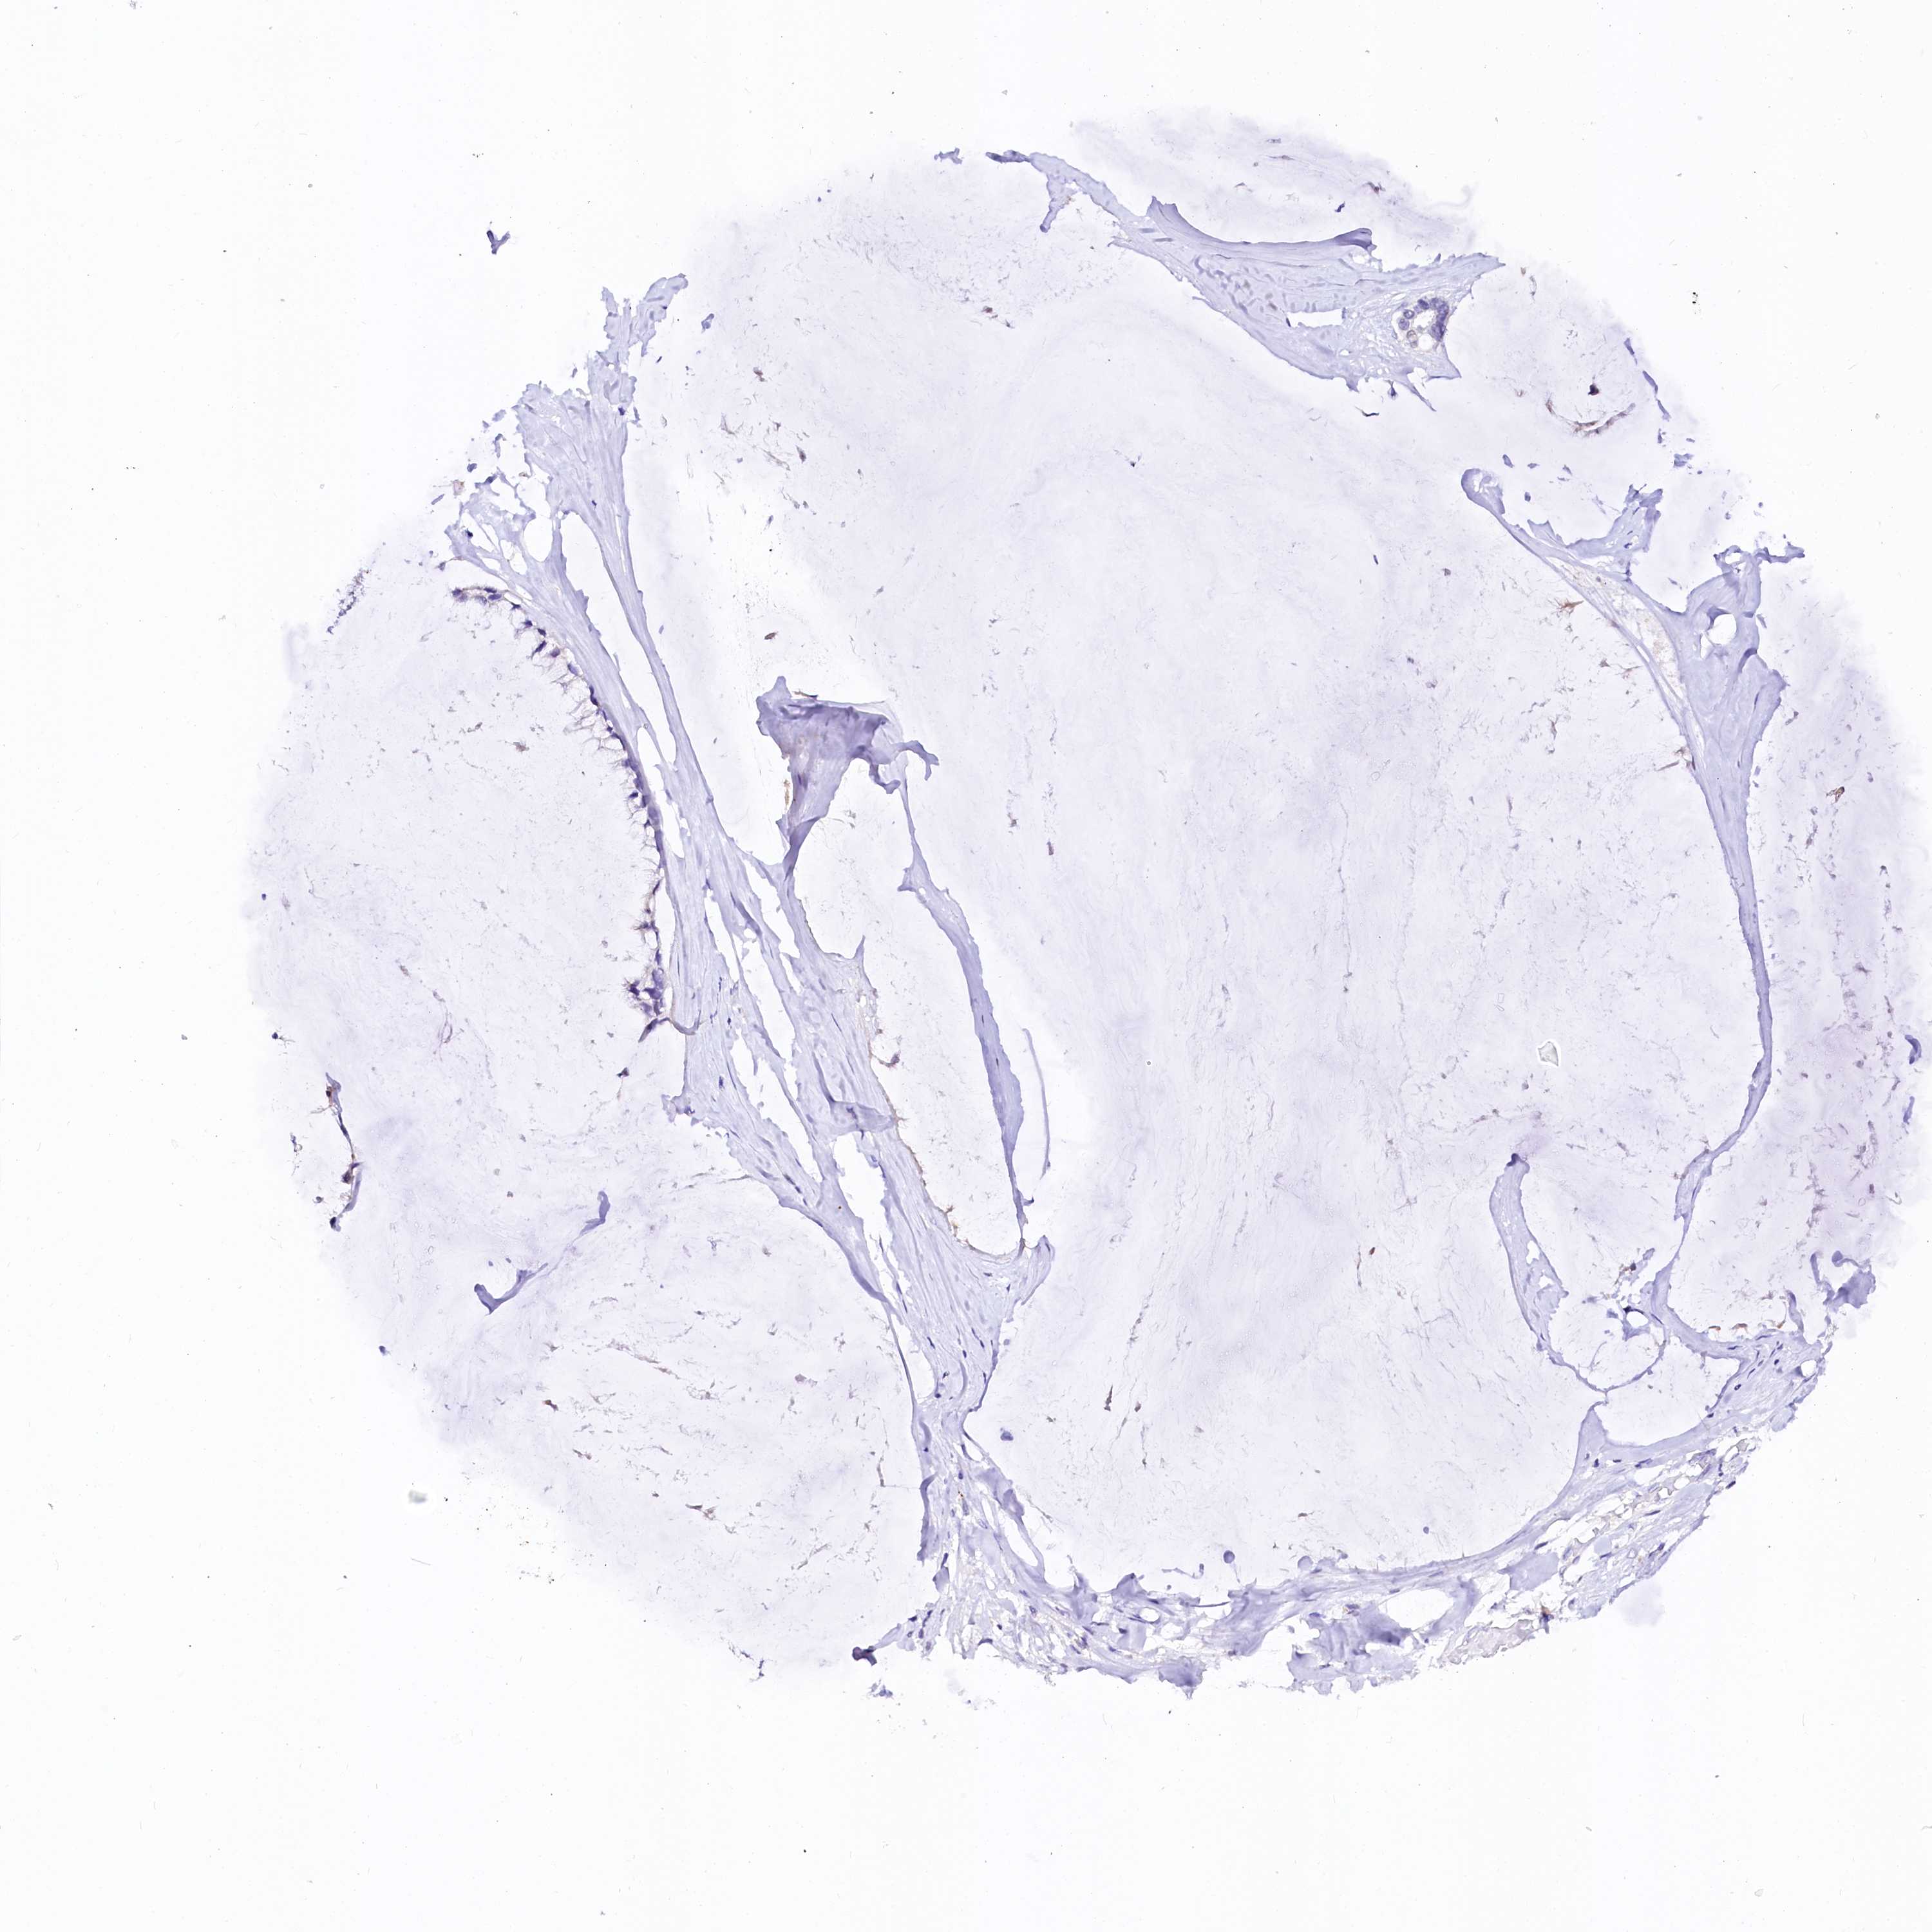

OVARIAN CANCER - Protein expressioni

A mouse-over function shows sample information and annotation data. Click on an image to view it in a full screen mode. Samples can be filtered based on level of antibody staining by selecting one or several of the following categories: high, medium, low and not detected. The assay and annotation is described here.

Note that samples used for immunohistochemistry by the Human Protein Atlas do not correspond to samples in the TCGA dataset.

Antibody stainingi

Antibody staining in the annotated cell types in the current human tissue is reported as not detected, low, medium, or high, based on conventional immunohistochemistry profiling in selected tissues. This score is based on the combination of the staining intensity and fraction of stained cells.

Each image is clickable and will lead to virtual microscopy that enables deeper exploration of all samples and also displays staining intensity scores, fraction scores and subcellular localization as well as patient and tissue information for each sample.

Antibody HPA039453

Staining

High

Medium

Low

Not detected

Intensity

Strong

Moderate

Weak

Negative

Quantity

>75%

75%-25%

<25%

None

Location

Nuclear

Cytoplasmic/membranous

Cytoplasmic/membranous,nuclear

Cystadenocarcinoma, serous, NOS

Carcinoma, endometroid

Cystadenocarcinoma, mucinous, NOS

Carcinoma, NOS